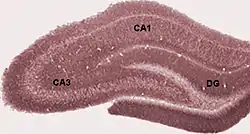

Diagrama de las regiones el hipocampo. DG: giro dentado. | ||

Sección coronal del encéfalo inmediatamente por delante de la protuberancia. El giro dentado está señalado abajo y a la izquierda. | ||